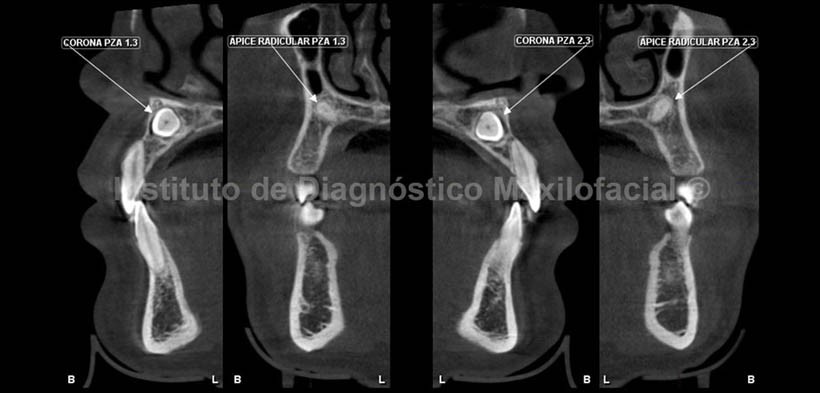

El estudio con tomografía volumétrica muestra en la reconstrucción panorámica( Fig. 1) la presencia de las piezas 1.3 y 2.3, las mismas que se encuentran impactadas entre sí.

Por otro lado, se evidencia la persistencia de las piezas 5.3 y 6.3; además de la alteración del tamaño en la pieza 1.8, compatible con microdoncia.

En cortes transaxiales (Fig. 2) se observa la corona de las pieza 1.3 próxima a la tabla vestibular, y su ápice en relación con la tabla palatina. Así mismo, la corona de la pieza 2.3 se observa próxima a la tabla palatina al igual que su ápice. En los cortes coronales (Fig.3) se observan las coronas de ambas piezas dentarias en estrecha relación con el conducto nasopalatino, el mismo que se observa parcialmente en esta imagen, además se aprecia la corona de la pieza 2.3 más inferior con respecto a la corona de la pieza 2.1 y el tercio medio radicular de ambas piezas se observa en relacioón con la cortical palatina.